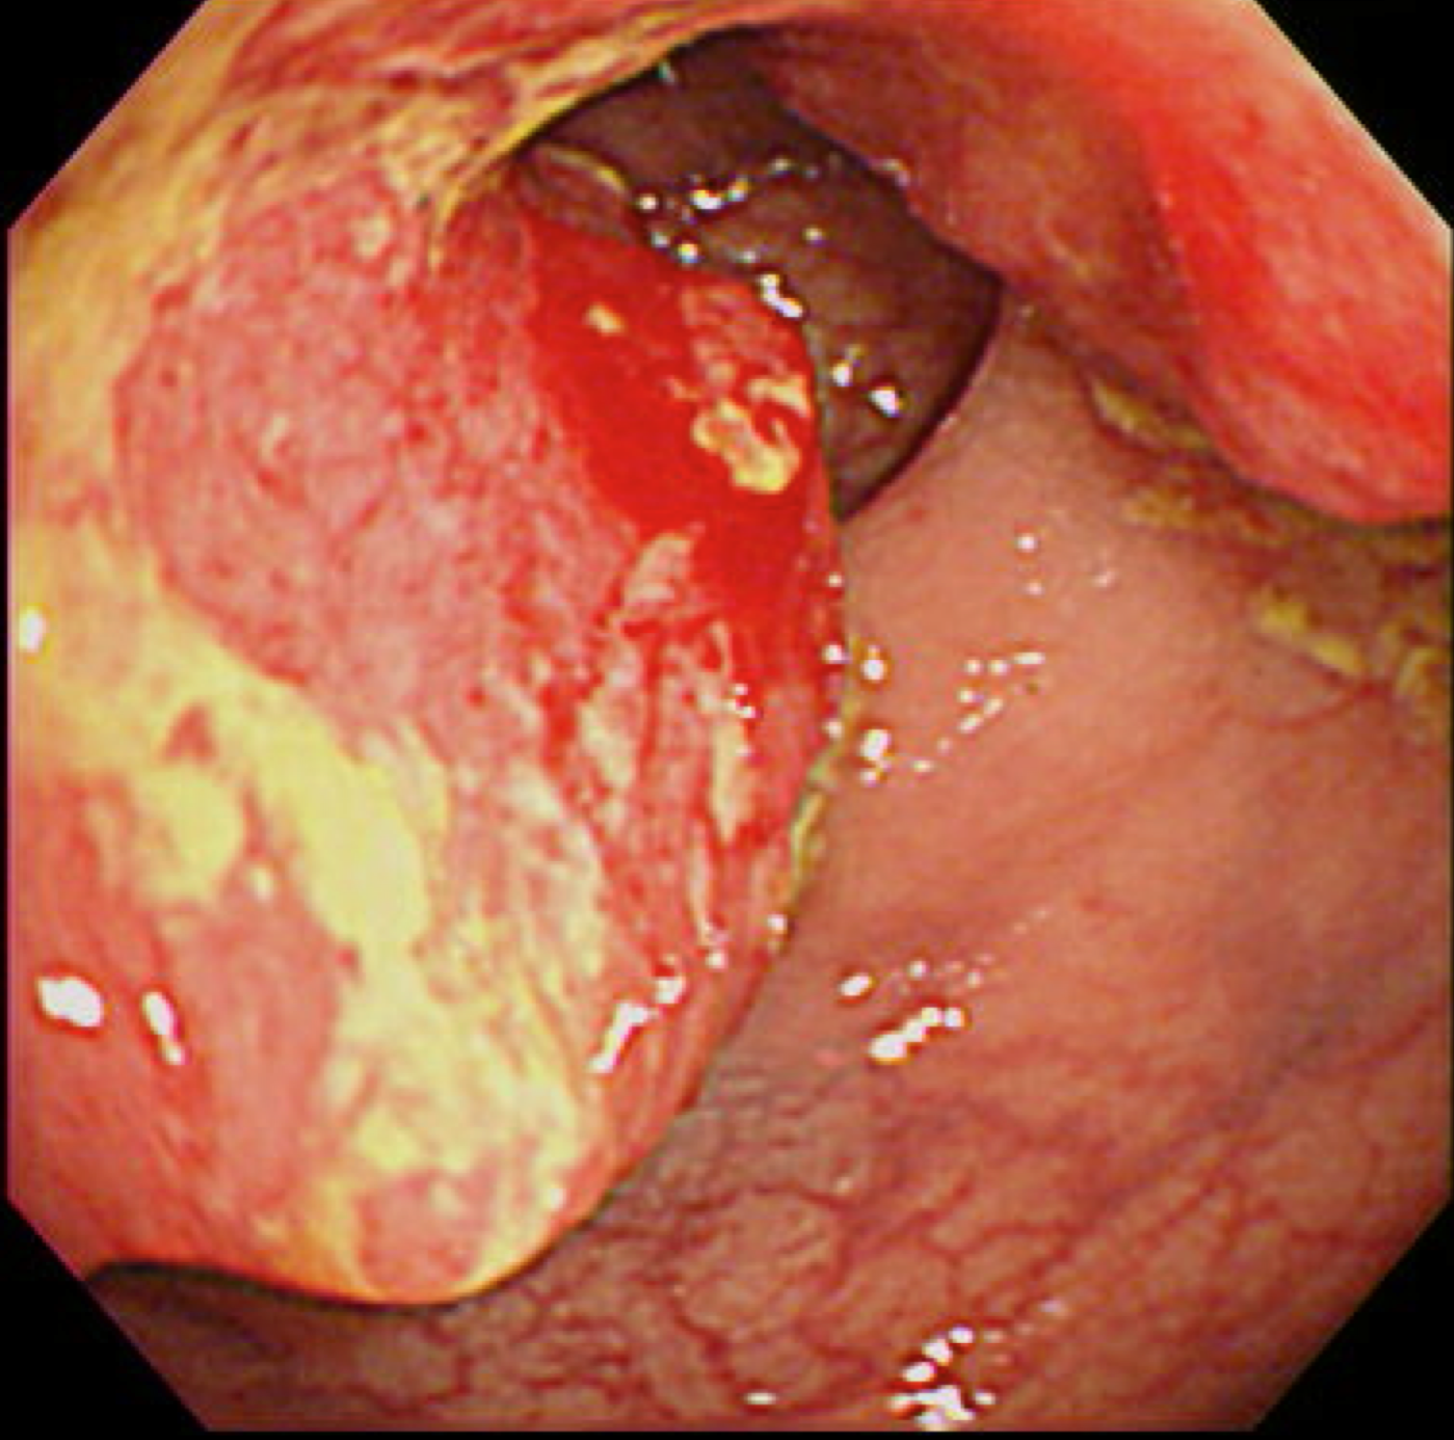

胃がん(上部消化管内視鏡)

食道がん(上部消化管内視鏡)

胃がん検診

富山市の胃がん検診は胃内視鏡(上部消化管内視鏡)もしくは胃透視(バリウムを飲む検査)でおこなわれています。胃がんはかつては日本人にとって非常に多いがんでしたが、ヘリコバクターの保菌者の減少とともに、胃がんも少なくなりつつあります。

胃がん検診では喉頭部・食道・十二指腸上部を観察します。

当院では胃内視鏡(経口)のみを実施しております。胃の中を十分に検査するために高解像度の内視鏡を使用しており、そのため口からの内視鏡検査となります。一般的に鼻からの経鼻内視鏡による検査の方が楽な検査と言われていますが、内視鏡が細い分、最新型の経口高解像度内視鏡に比べて解像度が落ちます。

富山市からの検診の案内には経鼻内視鏡のできる施設が明示されていますので、ご希望に合わせて受診してください。